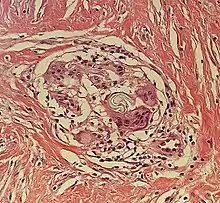

| Kaposi’s sarcoma in patch stage | The patch stage typically shows irregular proliferation of jagged vascular channels in the dermis below an integral epidermis. The so-called promontory sign is sometimes found in patch stage lesions and denotes vascular spaces surrounding pre-existing blood (see image).[23]

vessels |